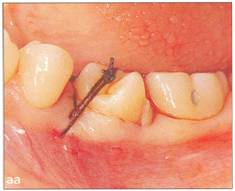

Fi 545e45f g 5-10 Stabilization of the donor tooth. The donor tooth has been splinted to the adjacent tooth with twisted wire and selfcured composite resin after etching and bonding. Fi 545e45f g 5-1 p After transplantation. |